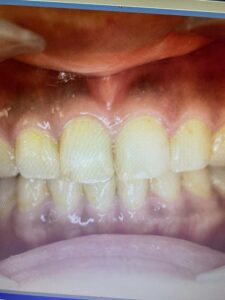

施術直後(2,3日はメラニンを浮き上がらせるので白くなります)

施術1週間後(白い上皮は剥がれ、きれいな歯茎になりました)

施術後2,3日は歯茎がピリピリするのですが、血行のよい健康的な歯茎になったと喜んでいただきました。